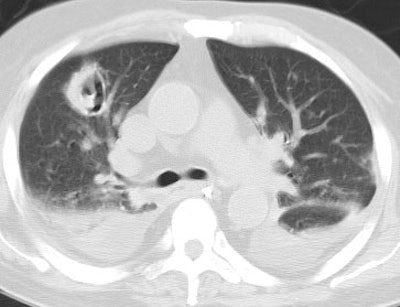

Invasive Aspergillosis:

Shown below is an immune compromised patient with invasive pulmonary Aspergillosis infection. CT scan demonstrated an air crescent reflecting air between the infarcted, retracted lung and the adjacent normal lung parenchyma. This is a late finding in Aspergillosis infection.